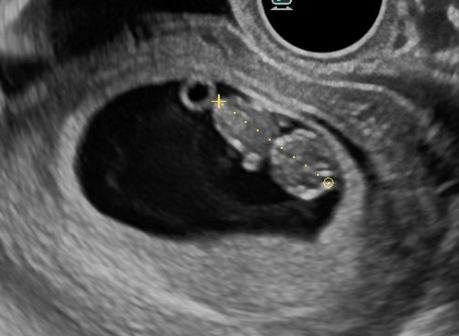

赤ちゃんがだんだんと人らしい見た目になっていきます。呼び名が「胎芽」から「胎児」になります。赤ちゃん(胎児)の頭からおしりまでの大きさを測ります。この時期に、分娩予定日を確定します。(※妊娠成立方法によっては、既に分娩予定日が確定されている方もいらっしゃいます。)